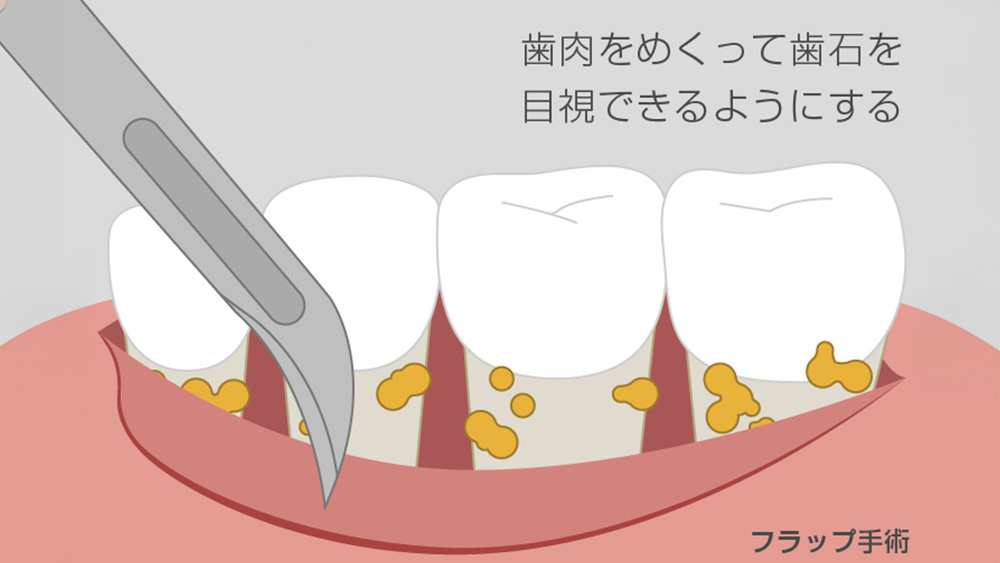

歯周病が進行し、歯周ポケットが深く、初期治療だけでは改善が難しい場合には、歯周外科治療を検討することがあります。

FOP法(歯肉剥離掻爬術)では、歯ぐきを一時的に開いて、深い部分の歯石や炎症組織を直接除去し、歯の根の清掃を徹底します。

また、複数の根を持つ奥歯では、ルートセパレーションによって、問題のある根だけを分離・切除し、残った健康な部分を温存する処置を行うこともあります。